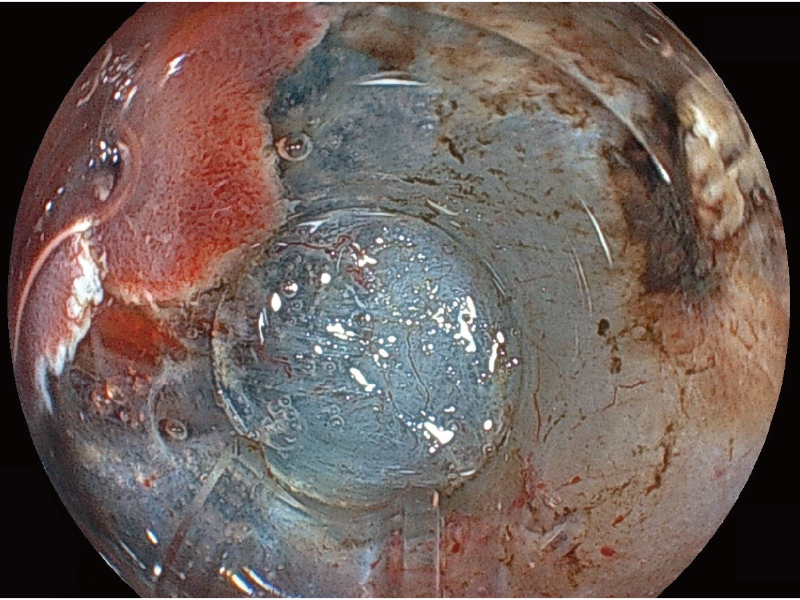

White Light Imaging

BLI (Blue Light Imaging)

*3 The images are not strictly close observation at 2 mm